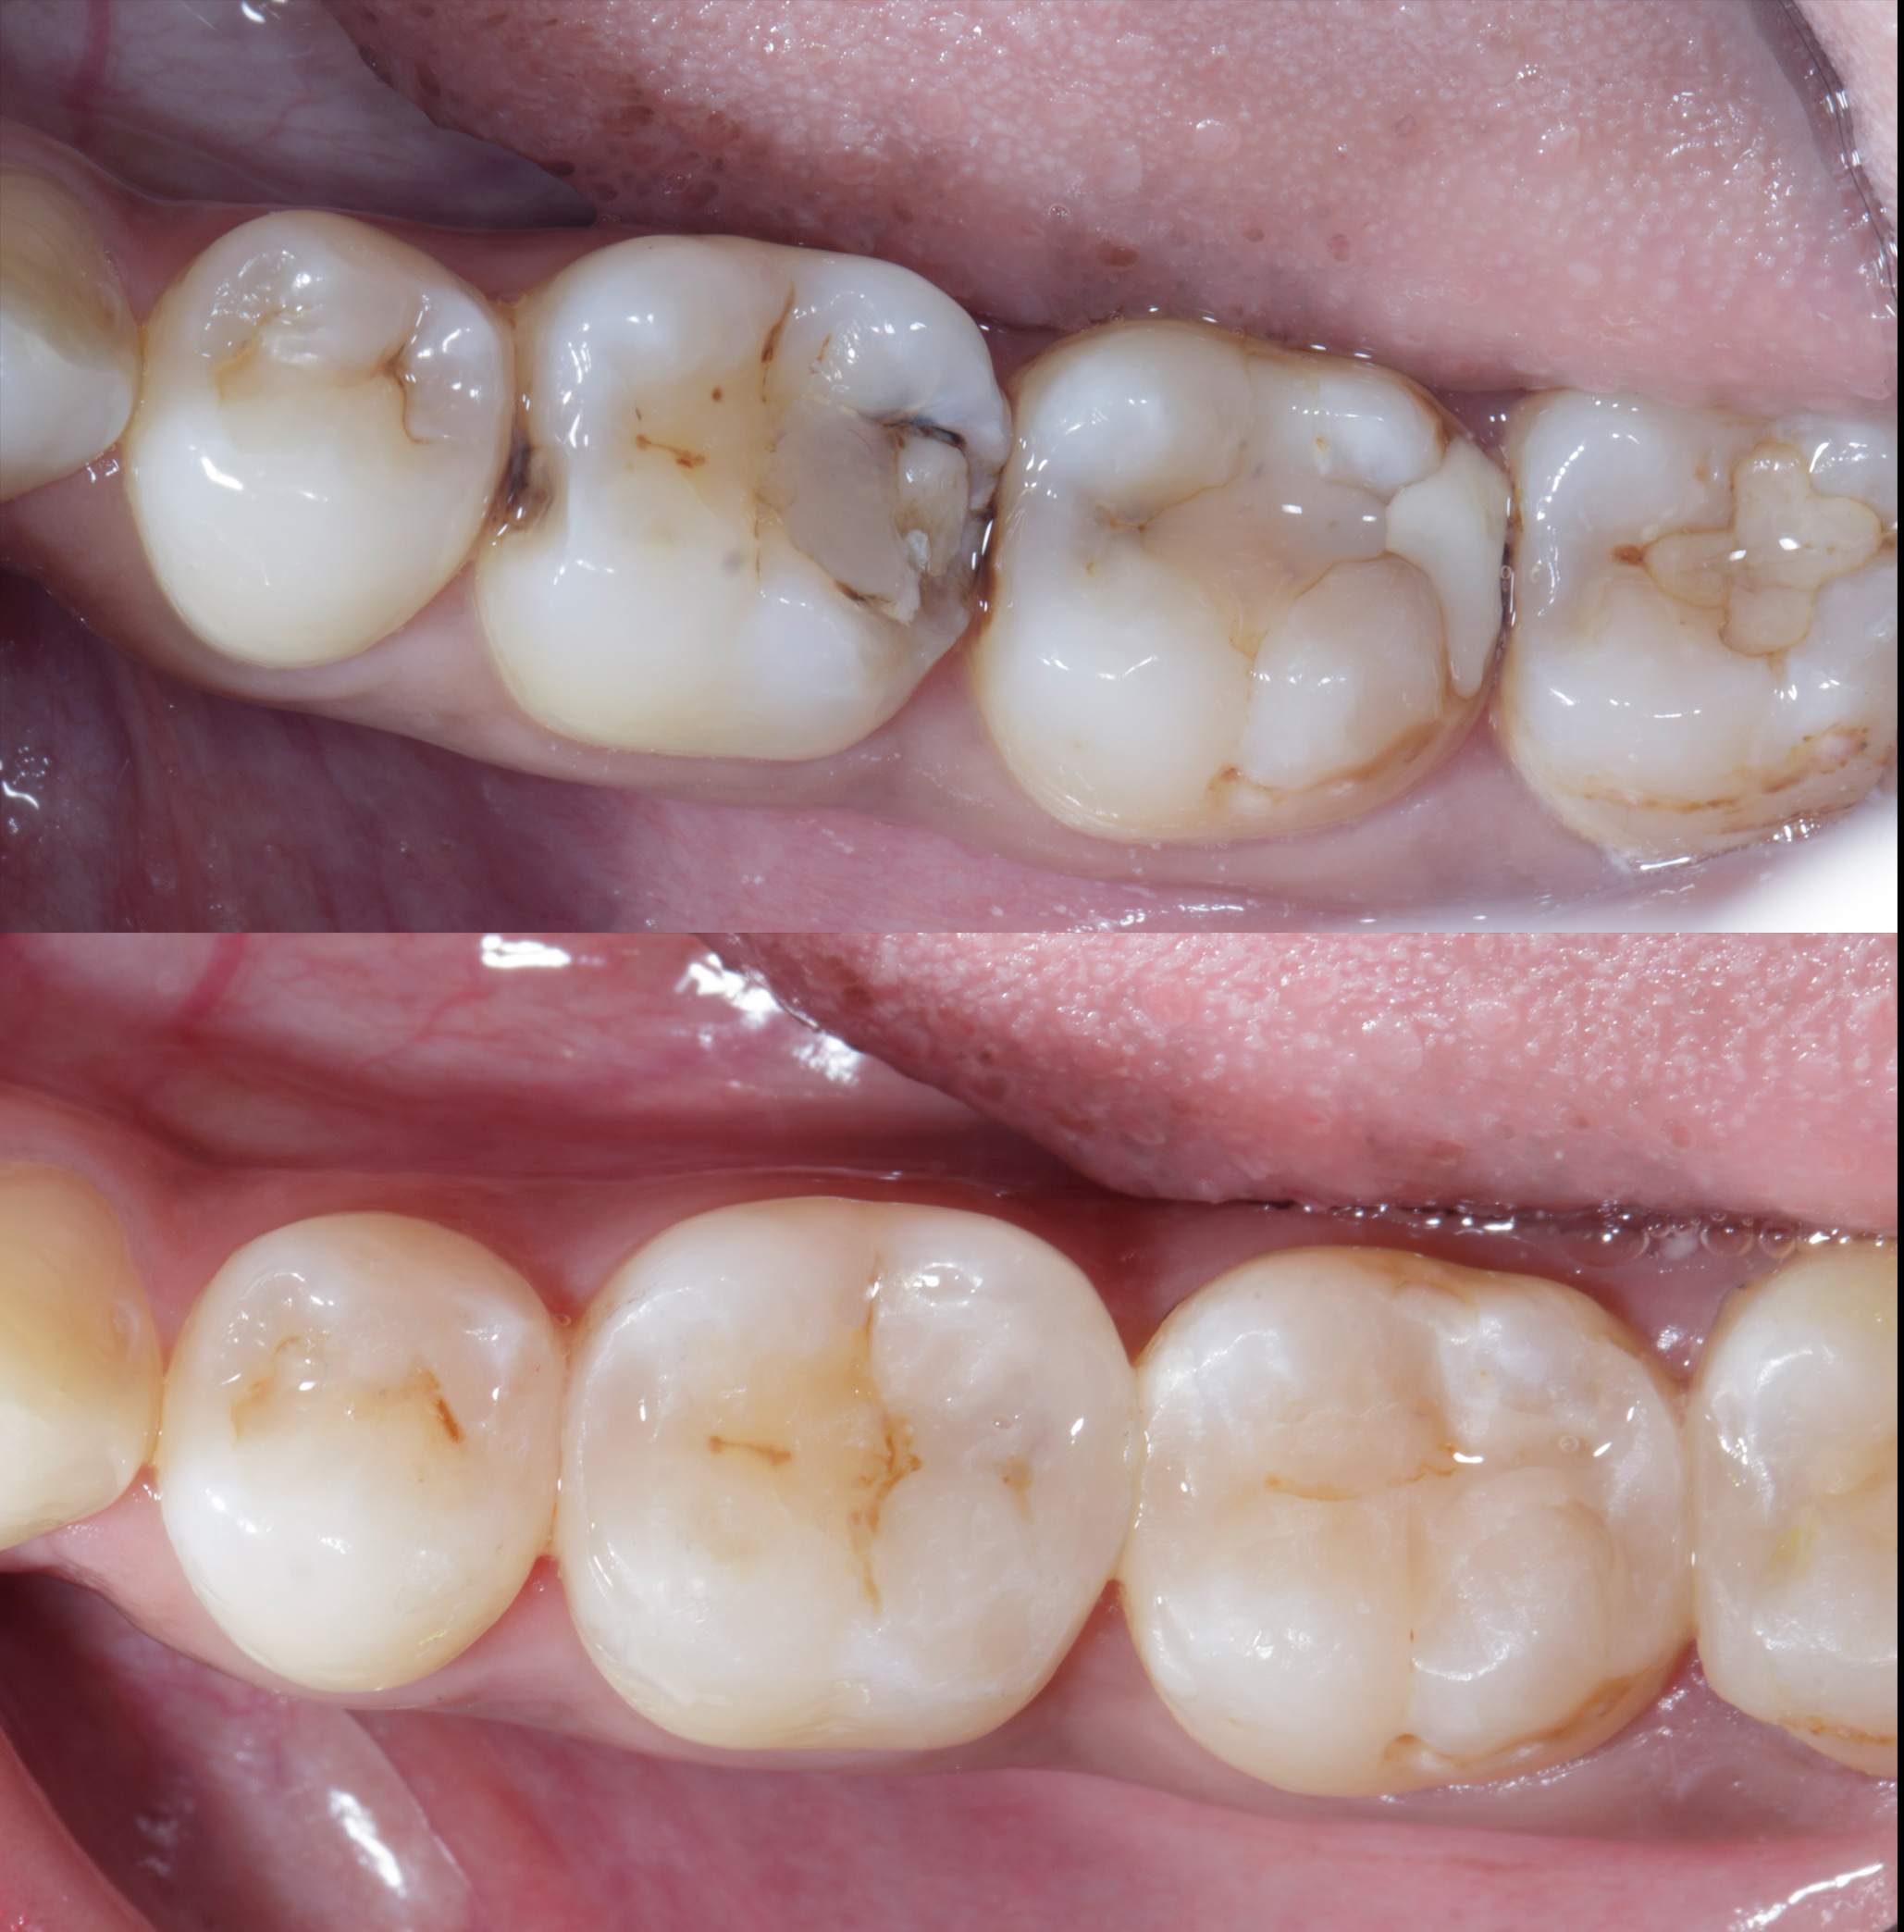

Figure 12

Figure 13

Figure 12. Post op after 15 days.Figure 13. Buccal view, Post of after 15 days shows healthy gums with papilla filled with ideal contacts and contours.

Figure 14

Figure 14. Before and after showing close to natural contacts / contours.